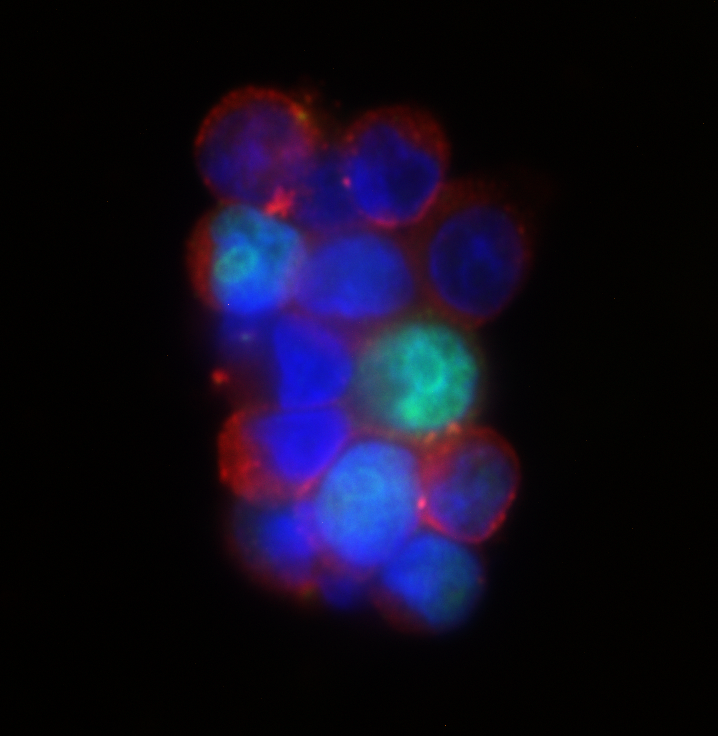

Distant metastasis is mostly initiated by tumor cells shed from the primary tumor into the blood circulation, known as circulating tumor cells (CTCs). Not all CTCs survive the harsh environment of circulation, but those that survive are carried to distant organs where metastatic tumors eventually arise. Advances in technologies have allowed us to be able to isolate CTCs from cancer patients. However, their biological properties which promote their survival and metastatic potential are still largely undefined. Our lab is interested in identifying the metastasis-initiating cells from the CTCs populations in patients and developing new therapeutic approaches for targeting them. The lab research focuses on two major topics: tumor intrinsic properties of CTCs that are capable of initiating metastasis and associated tumor extrinsic microenvironmental regulation which promotes this metastasis-initiating potential.

Brain metastasis dormancy and growth

We combine state-of-the-art single cell technologies with unique patient samples to identify dormancy and growth associated intrinsic and extrinsic factors specific to brain metastasis, and perform mechanistic studies to further validate and understand the related processes.